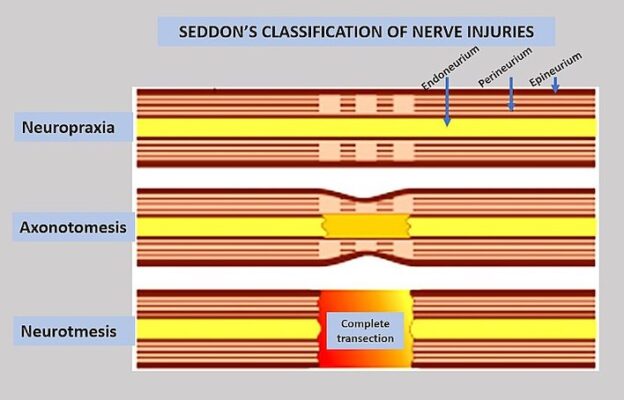

Hình 5: Phân độ Seddon cho tổn thương dây thần kinh

- Nếu dự đoán tiên lượng tốt, thì nên chờ đợi sự hồi phục với các biện pháp thích nghi và phòng ngừa tạm thời để giảm thiểu tác động chức năng cho đến khi hồi phục hoàn toàn. Cần loại bỏ áp lực lên vùng bị ảnh hưởng nếu có, và do đó cần lượng giá và sửa đổi các tư thế, hoạt động gây đè ép (như tránh ngồi bắt chéo chân, mặc quần quá bó, sửa đổi thành giường hoặc đệm bảo vệ quanh đầu gối, đặc biệt là khi ngủ,… ). Với giảm lực đè ép, các chấn thương thần kinh do gián đoạn tạm thời (neurapraxia) thường cải thiện đáng kể sau 6 tuần.

- Nếu tổn thương là do kéo căng sợi trục (Axonotmesis), quá trình phục hồi có thể mất nhiều thời gian hơn. Sợi trục mọc lại với tốc độ khoảng 1 mm /một ngày. Các cơ bị mất phân bố thần kinh hoàn toàn cần khoảng 18 tháng để phục hồi do tái phân bố. Tổn thương càng cao, càng có nhiều khả năng dẫn đến kết quả xấu đối với các cơ ở xa. Nếu tiên lượng xấu, thì nên lập kế hoạch thích ứng lâu dài và các chương trình phòng ngừa tại nhà, cũng như có thể cân nhắc phẫu thuật sớm, đặc biệt là ở trẻ em.